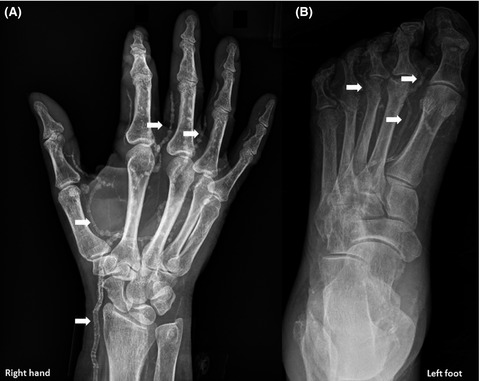

Arterial Calcification Due To Deficiency Of CD73

Otherwise known as ACDC (no, not the rock band, this is way less fun) this condition is when calcium accumulates very painfully in the blood vessels of the patient's hands and feet and is caused by a gene mutation. Only 9 people in the United States have this condition making it super rare!